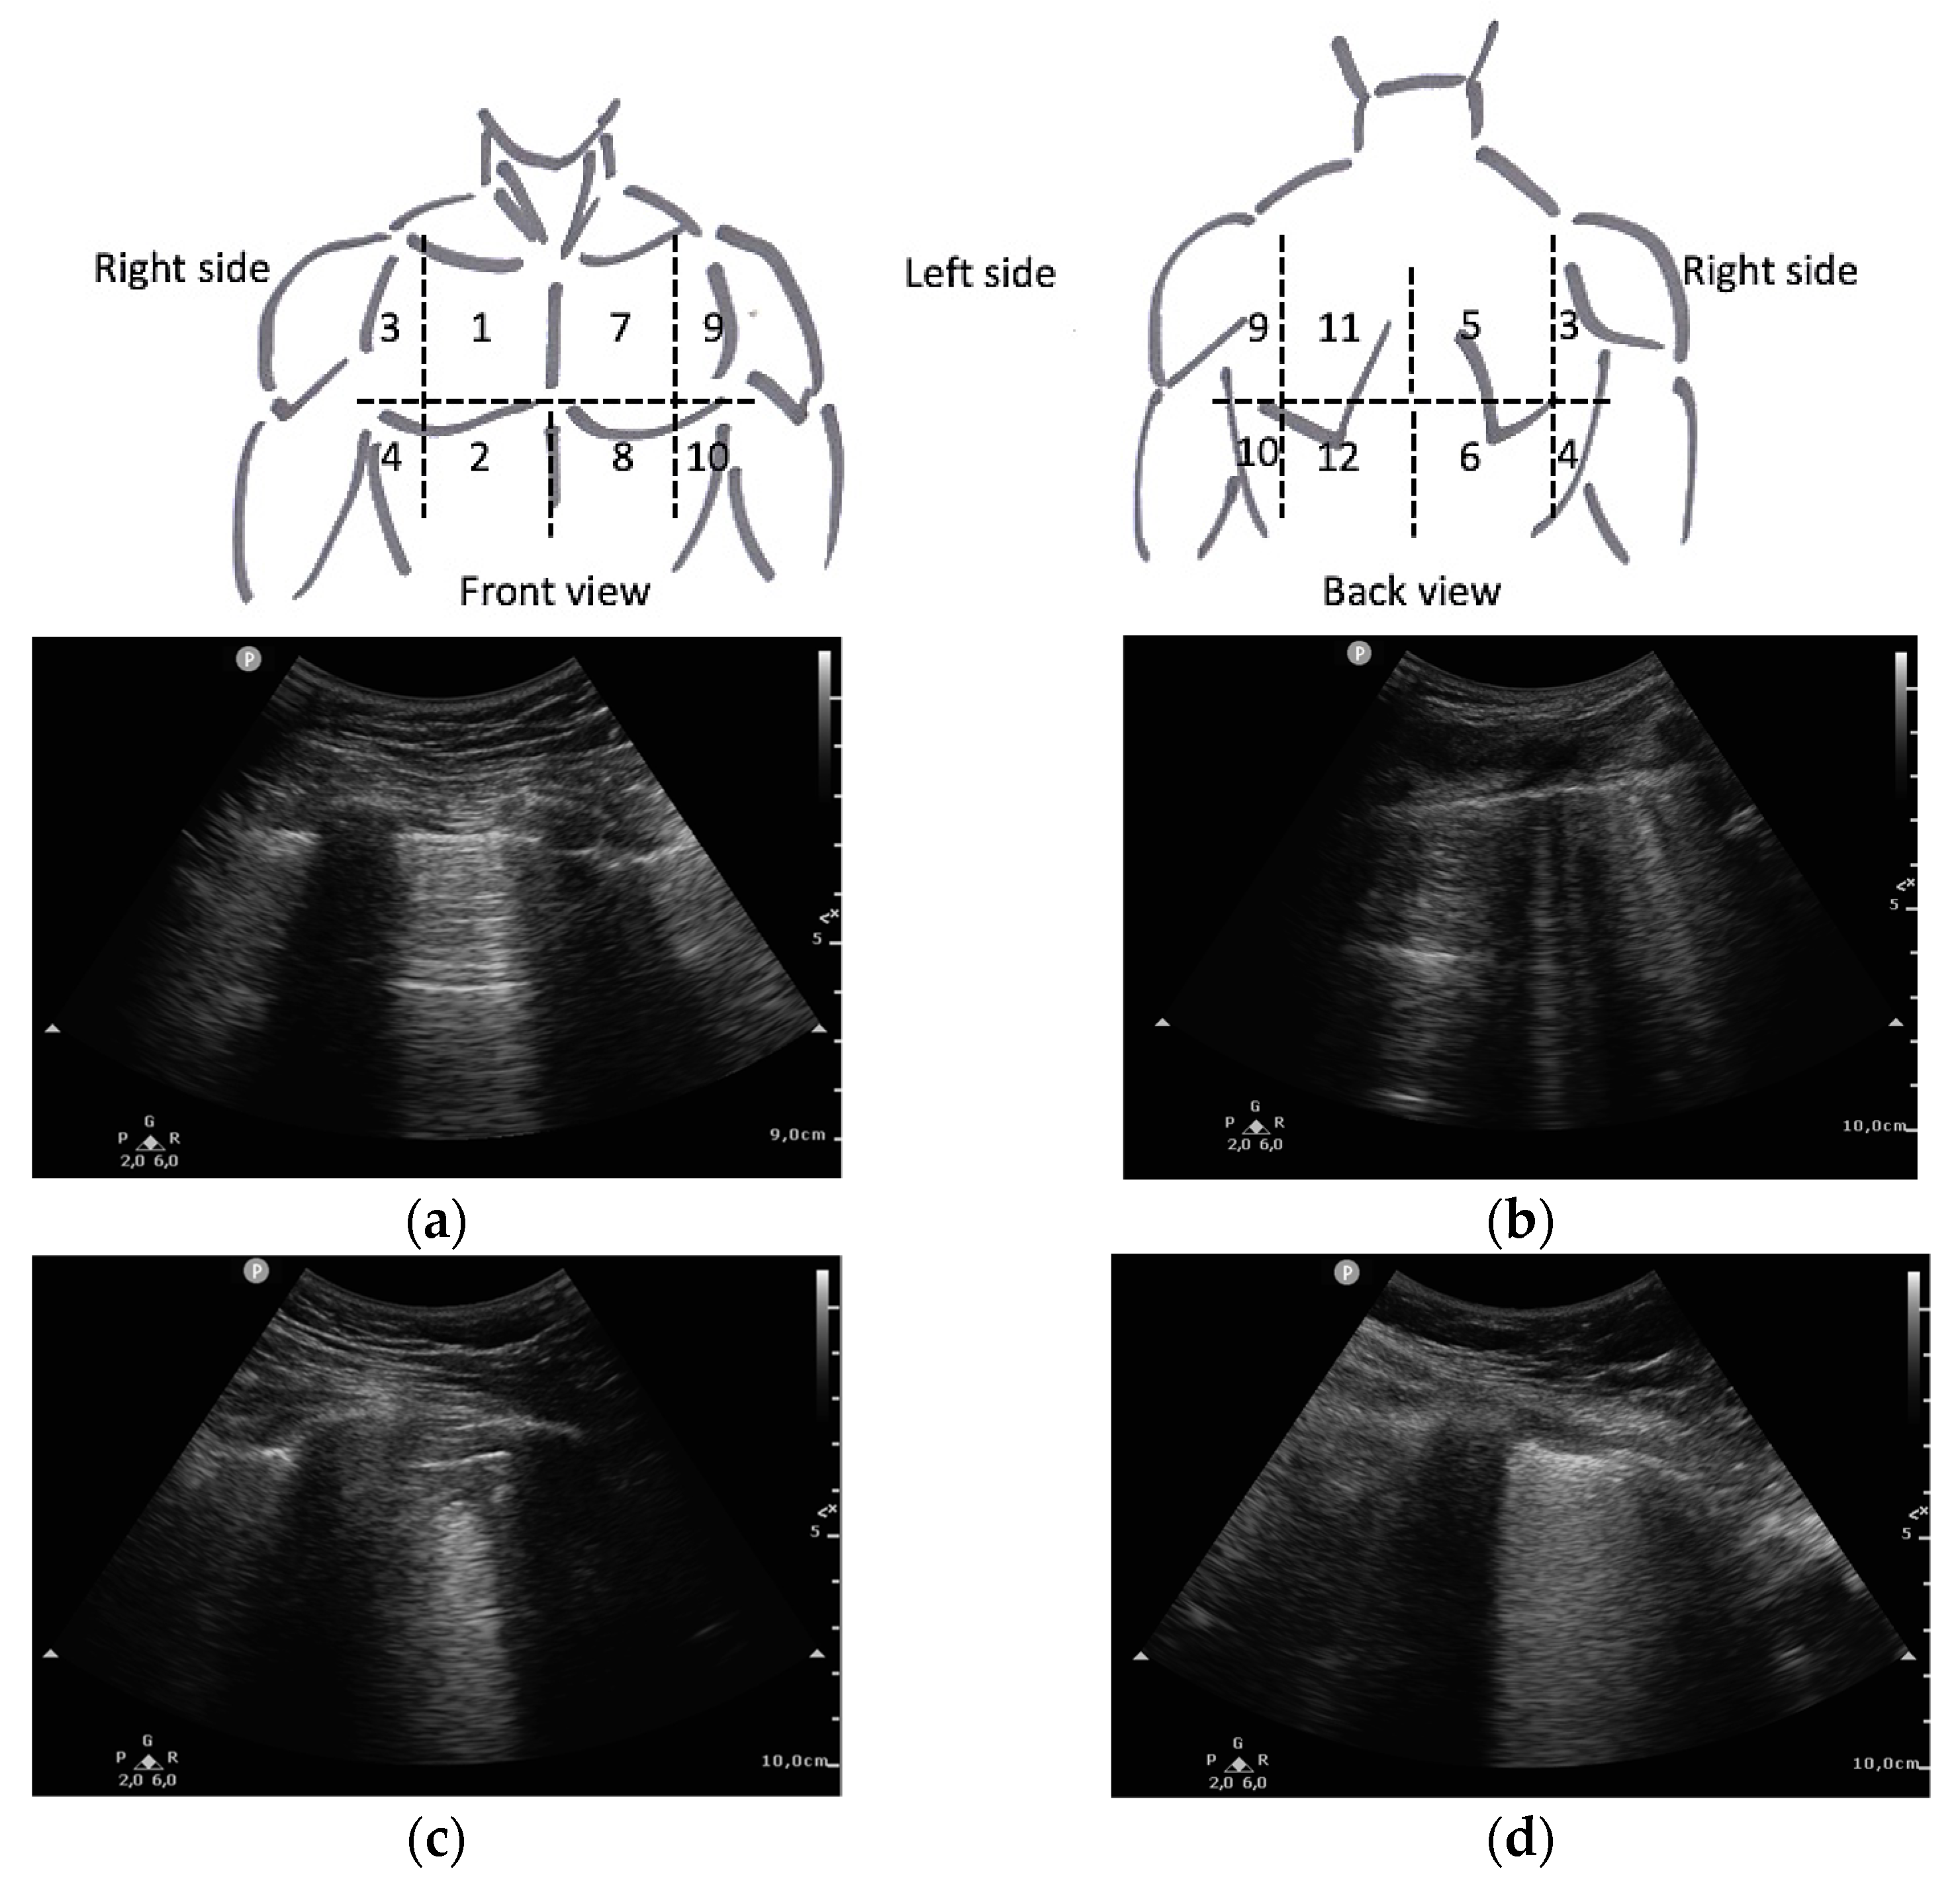

- Soldati, G.; Smargiassi, A.; Inchingolo, R.; Buonsenso, D.; Perrone, T.; Briganti, D.F.; Perlini, S.; Torri, E.; Mariani, A.; Mossolani, E.E.; et al. Proposal for International Standardization of the Use of Lung Ultrasound for Patients with COVID-19. J. Ultrasound Med. 2020, 39, 1413–1419. [Google Scholar] [CrossRef] [PubMed]

- Mento, F.; Perrone, T.; Macioce, V.N.; Tursi, F.; Buonsenso, D.; Torri, E.; Smargiassi, A.; Inchingolo, R.; Soldati, G.; Demi, L. On the Impact of Different Lung Ultrasound Imaging Protocols in the Evaluation of Patients Affected by Coronavirus Disease 2019. J. Ultrasound Med. 2021, 40, 2235–2238. [Google Scholar] [CrossRef]